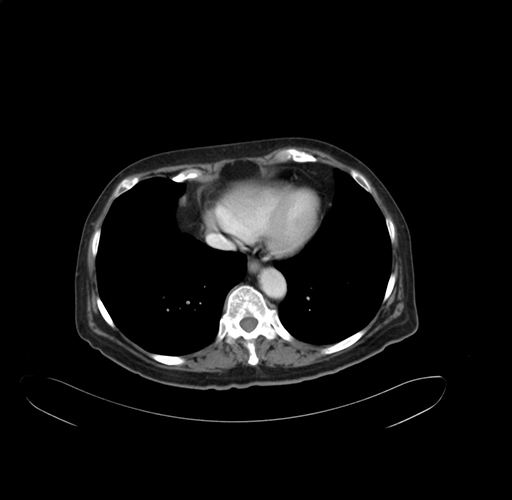

Pre-Chemo: Coronal Venous